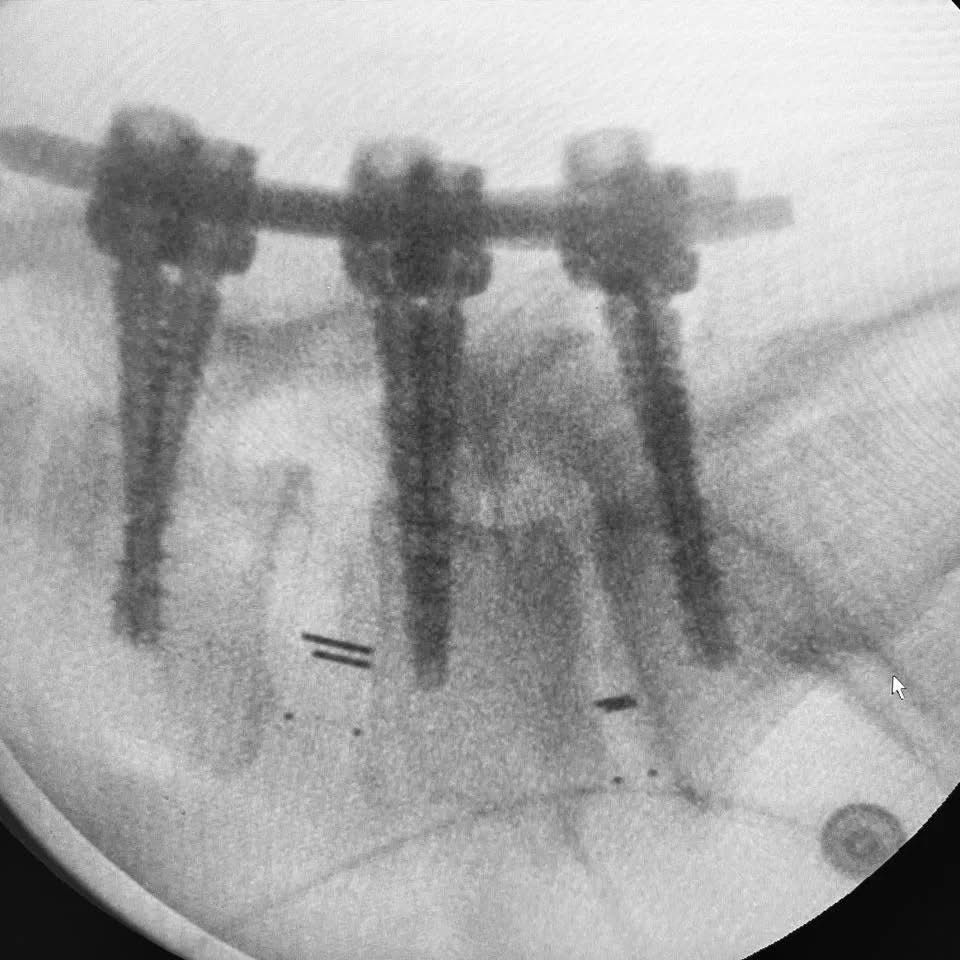

Cirugía de columna por mínima invasión

Estabilización y fusión lumbar con tornillos transpediculares